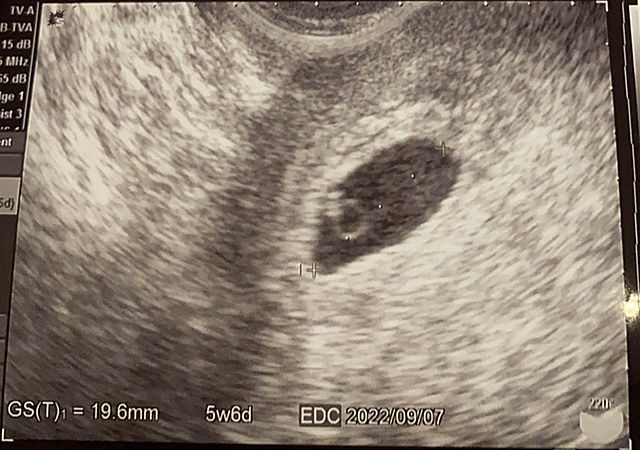

今日、産婦人科行ってきました!! うちのお腹には‥ 6週目に入る赤ちゃんが 心臓が動いてた! めっちゃ感動やった! 来月で結婚一年になりますが! その前に赤ちゃんが産まれる(笑) 今は、子宮の違和感と戦ってます(笑) 元気に‥ 産まれてきてください! 愛しいうちと旦那のベイビーちゃん!!